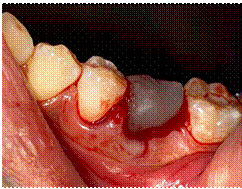

de 3 minutos (Figura 4).

Figura 4.

Prueba de guía quirúrgica en alveolo receptor.